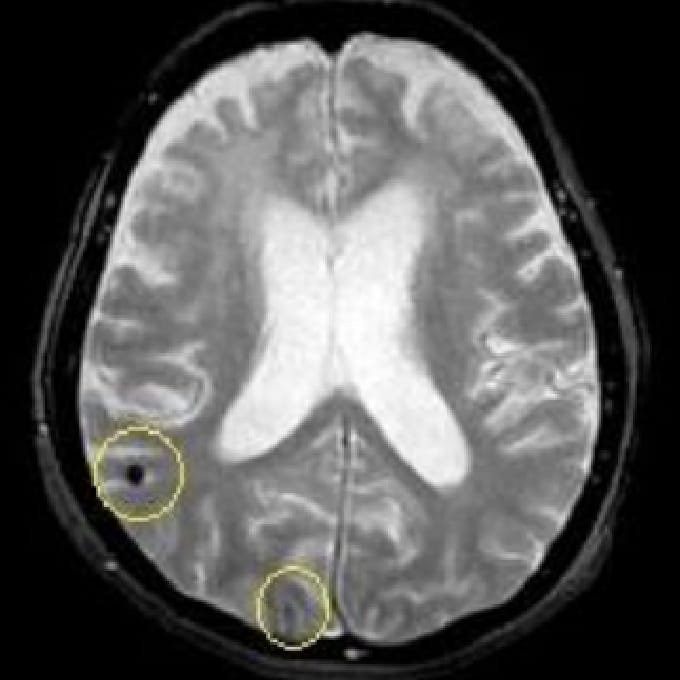

微小出血

MRIは、脳の断面画像を撮影し、脳そのものの状態を確認する検査です。X線を使用せず、脳梗塞の痕跡(無症候性を含む)や出血の跡、腫瘍などの異常がないかを調べます。MRAはMRIの撮影法の一つで、脳や頸部の血管を画像として写し出し、血管の形や流れの状態を確認する検査です。未破裂脳動脈瘤の疑い、血管の狭窄・閉塞など、脳卒中リスクにつながる所見の確認に役立ちます。